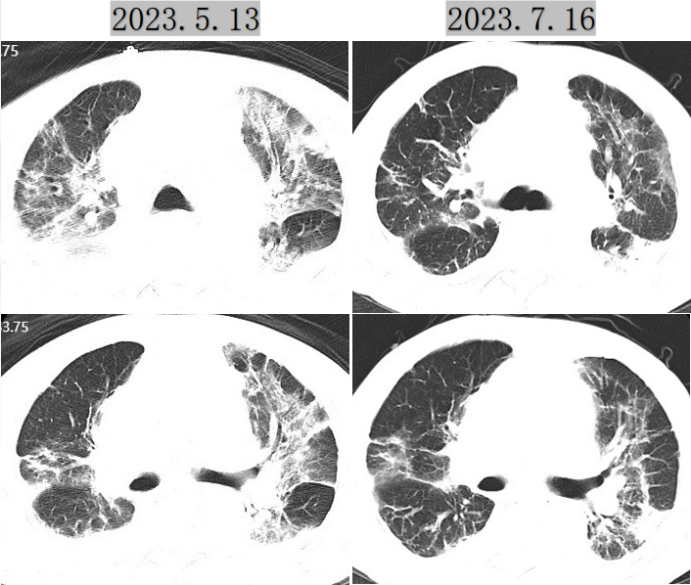

患者:76岁男性,因“咳嗽咳痰10天,发热1天”于2023年5月13日入院。

病原学:新型冠状病毒核酸阳性,甲流及乙流核酸阳;痰培养示肺炎克雷伯菌(CRE株,对亚胺培南耐药);胸部CT示双肺实变影。

7月6日、7月9日新冠核酸连续阴性,7月16日复查胸部CT提示肺部炎症较前明显改善,患者感染控制,病情好转(图5)

图片

5  患者胸部CT对比